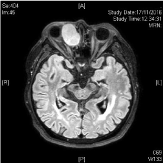

A 62 year old Chinese male presented with a 3-month history of right epiphora and blurring of vision. On examination, right eye hyperglobus (Figure 1) was noted and pupillary examination showed a relative afferent papillary defect. On palpation there was firmness over the right lower eyelid. Flexible nasendoscopy was unremarkable and no mass was noted in the inferior meatus. MRI and CT orbits revealed a 3.6cm mass centred in the right lacrimal sac with extension into the proximal right nasolacrimal duct. Mass effect and indentation of medial aspect of right globe was noted, displacing it superolaterally, there was no signal abnormality or enhancement in adjacent orbital fat (Figures 3-5). He underwent an endoscopic biopsy and histology showed a spindle cell tumour (Figure 2). Decision was made for surgical resection of the tumour. Patient underwent a right lateral rhinotomy and excision of right lacrimal sac tumour. Intraoperatively, a 3cm right lacrimal sac tumour was noted with a clear plane between tumour and right periorbita laterally. The tumour did not breach the skull base (Figure 6a and 6b).

Figure 5: MRI T1 weight image of right lacrimal sac tumour, axial cut